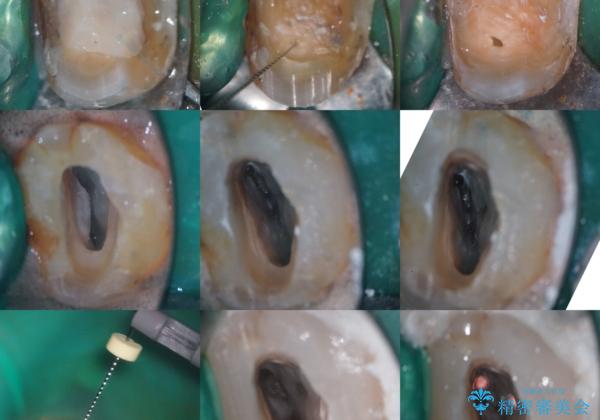

【根管治療】ズーンと痛い歯の治療。

- 奥歯付近がジーンと痛いことを主訴に来院されました。

左上7番の歯は、歯髄検査にて反応を示し、歯周ポケットはありませんでした。

親知らず抜歯を行い、痛みの変化や歯根吸収の有無を確認したのち、抜髄処置を行っています。

症状改善し、遠心の骨の回復も認めます。

バイオセラミックシーラーを使用して根管充填を行っています。